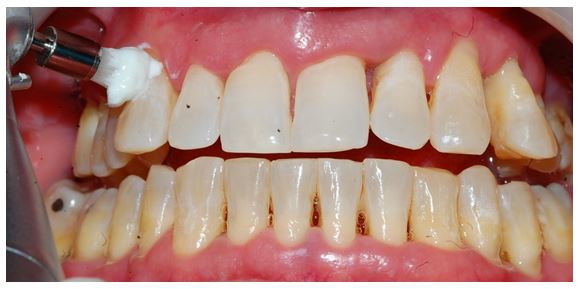

A 45-year-old male patient with no systemic illness exhibited severe DH symptoms bilaterally in canine and premolar teeth due to periodontal recessions. A clinical examination revealed the presence of biofilm, gingival recession, and periodontal pocketing on the buccal surfaces of the upper and lower premolars, as well as the superior and inferior molars (Figure 1). Schiff Air Index (SAI) was performed in the teeth 13, 14, 15,23, 24, and 25 by applying air jet to each tooth’s vestibular surface for 5 seconds after and before the prophylaxis protocol according sensitivity scale: 0 = Tooth/subject does not show sensitivity in response to air stimulation; 1 = Tooth/subject responds to air stimulus, but does not request discontinuation of stimulus; 2 = Tooth/subject responds to air stimulus, and requests discontinuation or moves from stimulus; 3 = Tooth/subject responds to stimulus, consider stimulus to be painful, and requests discontinuation of the stimulus [6].

Figure 1: The patient’s initial view from the authors’ source.